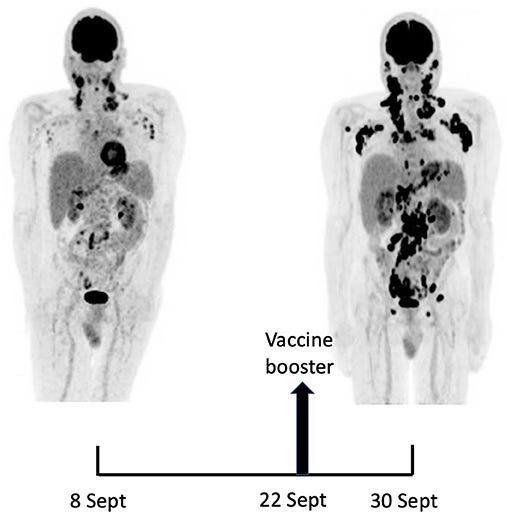

Related to the above research, we have from 2021: “Rapid Progression of Angioimmunoblastic T Cell Lymphoma Following BNT162b2 mRNA Vaccine Booster Shot: A Case Report”18:

The remarkable efficiency of nucleoside-modified SARS-CoV-2 mRNA vaccines has been related to their ability to induce a potent stimulation of T follicular helper (TFH) cells, resulting in persistent germinal center B cell responses (1, 2). Clinically, this might translate into reactive lymphoadenopathy which sometimes may raise a differential diagnosis with a lymphoproliferative disorder (3, 4). At the same time, the possible impact of SARS-CoV-2 mRNA vaccination on pre-existing peripheral T cell lymphoma is still to be determined.

A 66-year-old man with no significant medical history except for hypertension, hypercholesterolemia and type 2 diabetes presented on September 1, 2021 with cervical lymphadenopathies that became recently apparent during a flu-like syndrome. The two doses of BNT162b2 mRNA vaccine had been administered, respectively, 5 and 6 months earlier in the left deltoid. Besides moderate asthenia, he did not report any constitutional symptom. Blood examination indicated a mild inflammatory syndrome, without anemia or white blood cell changes; Lymphocytes immunophenotyping was unremarkable. Protein electrophoresis and immunoglobulin levels were normal and Coombs test was negative.

A 18F-FDG PET/CT revealed multiple voluminous hypermetabolic lymphadenopathies above and below the diaphragm as well as several extra-nodal hypermetabolic lesions (Figure 1, left panel). Considering a presumptive diagnosis of stage IV lymphoma, a left cervical lymph node biopsy was performed. Pathological examination revealed residual atrophic germinal centers, surrounded by an expanded paracortical area composed of an atypical T-cell infiltrate with clear cell morphology, expressing TFH cell markers (CD3, CD4, PD1, ICOS, BCL6, CXCL13) and a loss of CD7. The paracortical area contained an increased number of high-endothelial venules, supported by an increased number of follicular dendritic cell networks, with some foci of EBV+ B-cell immunoblastic proliferation in the background (Figure 2). These features highly suggested a diagnosis of AngioImmunoblastic T cell Lymphoma (AITL), pattern 2. Next generation sequencing (NGS) performed on the biopsy specimen identified the RHOA G17V mutation characteristic of AITL (5) together with the DNMT3A, IDH2 and TET2 mutations. A TCR-gamma gene rearrangement confirmed a clonal T cell proliferation. Altogether, these findings unambiguously established the diagnosis of AITL. A bone marrow biopsy did not reveal neither morphological nor phenotypic abnormalities, but NGS revealed DMNT3A and TET2 mutations in bone marrow cells with allele frequencies of 41% and 36%, respectively.

Fourteen days after the PET/CT, a booster dose of the BNT162b2 mRNA vaccine was administered in the right deltoid in preparation of the first cycle of chemotherapy. Within a few days following the vaccine booster, the patient reported noticeable swelling of right cervical lymph nodes. In order to get a baseline close to the initiation of the therapy, a second 18F-FDG PET/CT was performed 8 days after the vaccine booster administration, i.e. 22 days after the first one.

This wasn’t just stimulating the TFH cells, it was tumorigenic in action:

It demonstrated a clear increase in number, size and metabolic activity of pre-existing lymphadenopathies at the supra- and sub-diaphragmatic level. Furthermore, new hypermetabolic lymphadenopathies and new hypermetabolic sites had developed since the first examination, in several different locations (Figure 1, right panel).

Total lesion glycolysis (TLG), which measures metabolic activity, was used to monitor changes in lymph node activities:

As compared with the initial test, there was a marked 5.3-fold increase in whole-body TLG, with the increase in the post-booster test being twice higher in the right axillary region than in the left one. In parallel, a mild increase in blood levels of ferritin, C-reactive protein and LDH were noted.

To the best of our knowledge, this is the first observation suggesting that administration of a SARS-CoV-2 vaccine might induce AITL progression. Several arguments support this possibility. First, the dramatic speed and magnitude of the progression manifested on two 18F-FDG PET-CT performed 22 days apart. Such a rapid evolution would be highly unexpected in the natural course in the disease. Since mRNA vaccination is known to induce enlargement and hypermetabolic activity of draining lymph nodes, it is reasonable to postulate that it was the trigger of the changes observed. Indeed, the increase in size and metabolic activity was higher in axillary lymph nodes draining the site of vaccine injection as compared to their contralateral counterparts. However, pre-existing lymphomatous nodes were also clearly enhanced as compared to the first test. Moreover, new hypermetabolic lesions most likely of lymphomatous nature clearly appeared at distance of the injection site.